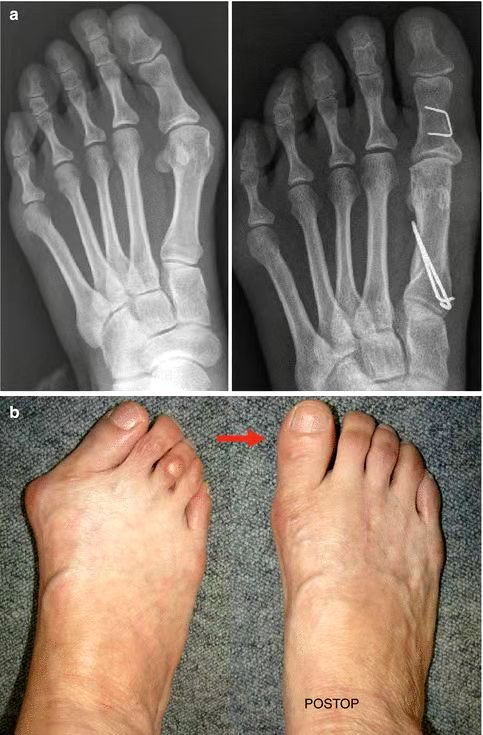

对于脚本身,踮脚姿势增加前脚掌压力(特别是拇趾周围),加上很多尖鞋头挤住脚趾,会改变足弓高度,使拇外翻风险升高1~2倍,还可能导致足底筋膜炎及骨骼变形[1, 8, 9]。

左侧为拇外翻X线片及足部照片,右侧为术后丨参考文献[10]